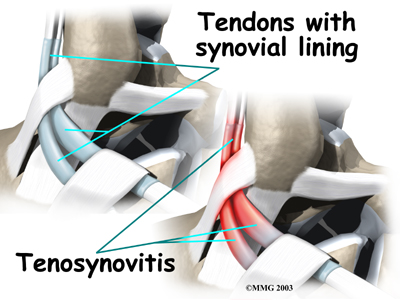

Peroneal tendon problems mostly occur where the tendons glide within the pulley behind the lateral malleolus. Their movement can cause irritation of the lining of the tendons. This condition is called . The irritation can also occur after an ankle injury, such as a blow to the outside of the ankle or an ankle sprain.

Peroneal tendon problems mostly occur where the tendons glide within the pulley behind the lateral malleolus. Their movement can cause irritation of the lining of the tendons. This condition is called . The irritation can also occur after an ankle injury, such as a blow to the outside of the ankle or an ankle sprain.

Peroneal tendon problems mostly occur where the tendons glide within the pulley behind the lateral malleolus. Their movement can cause irritation of the lining of the tendons. This condition is called

Peroneal tendon problems mostly occur where the tendons glide within the pulley behind the lateral malleolus. Their movement can cause irritation of the lining of the tendons. This condition is called